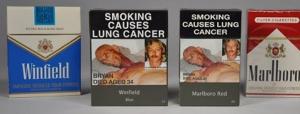

Actualité publiée il y a 10 années 3 moisCIGARETTES: Avec le paquet neutre, toutes les marques sont aussi nocives